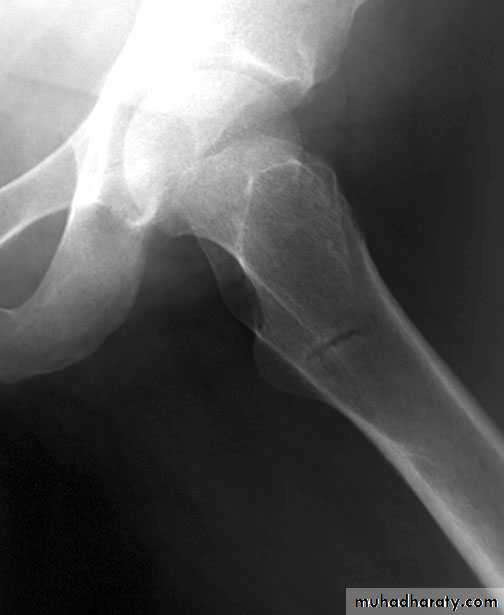

Osteomalacia: Bone scanRadiographic features

1-Generalized osteopenia2-Looser's zones (pseudofractures):

cortical stress fractures filled with

poorly mineralized osteoid tissue.

* Milkman's syndrome: osteomalacia

with many Looser's zones

Typical location of Looser's zones

(often symmetrical)

Axillary margin of scapula

Inner margin of femoral neck

Rib

Pubic, ischial rami

* Osteomalacia may be indistinguishable from osteoporosis; however, Looser's

zones are a reliable differentiating feature.